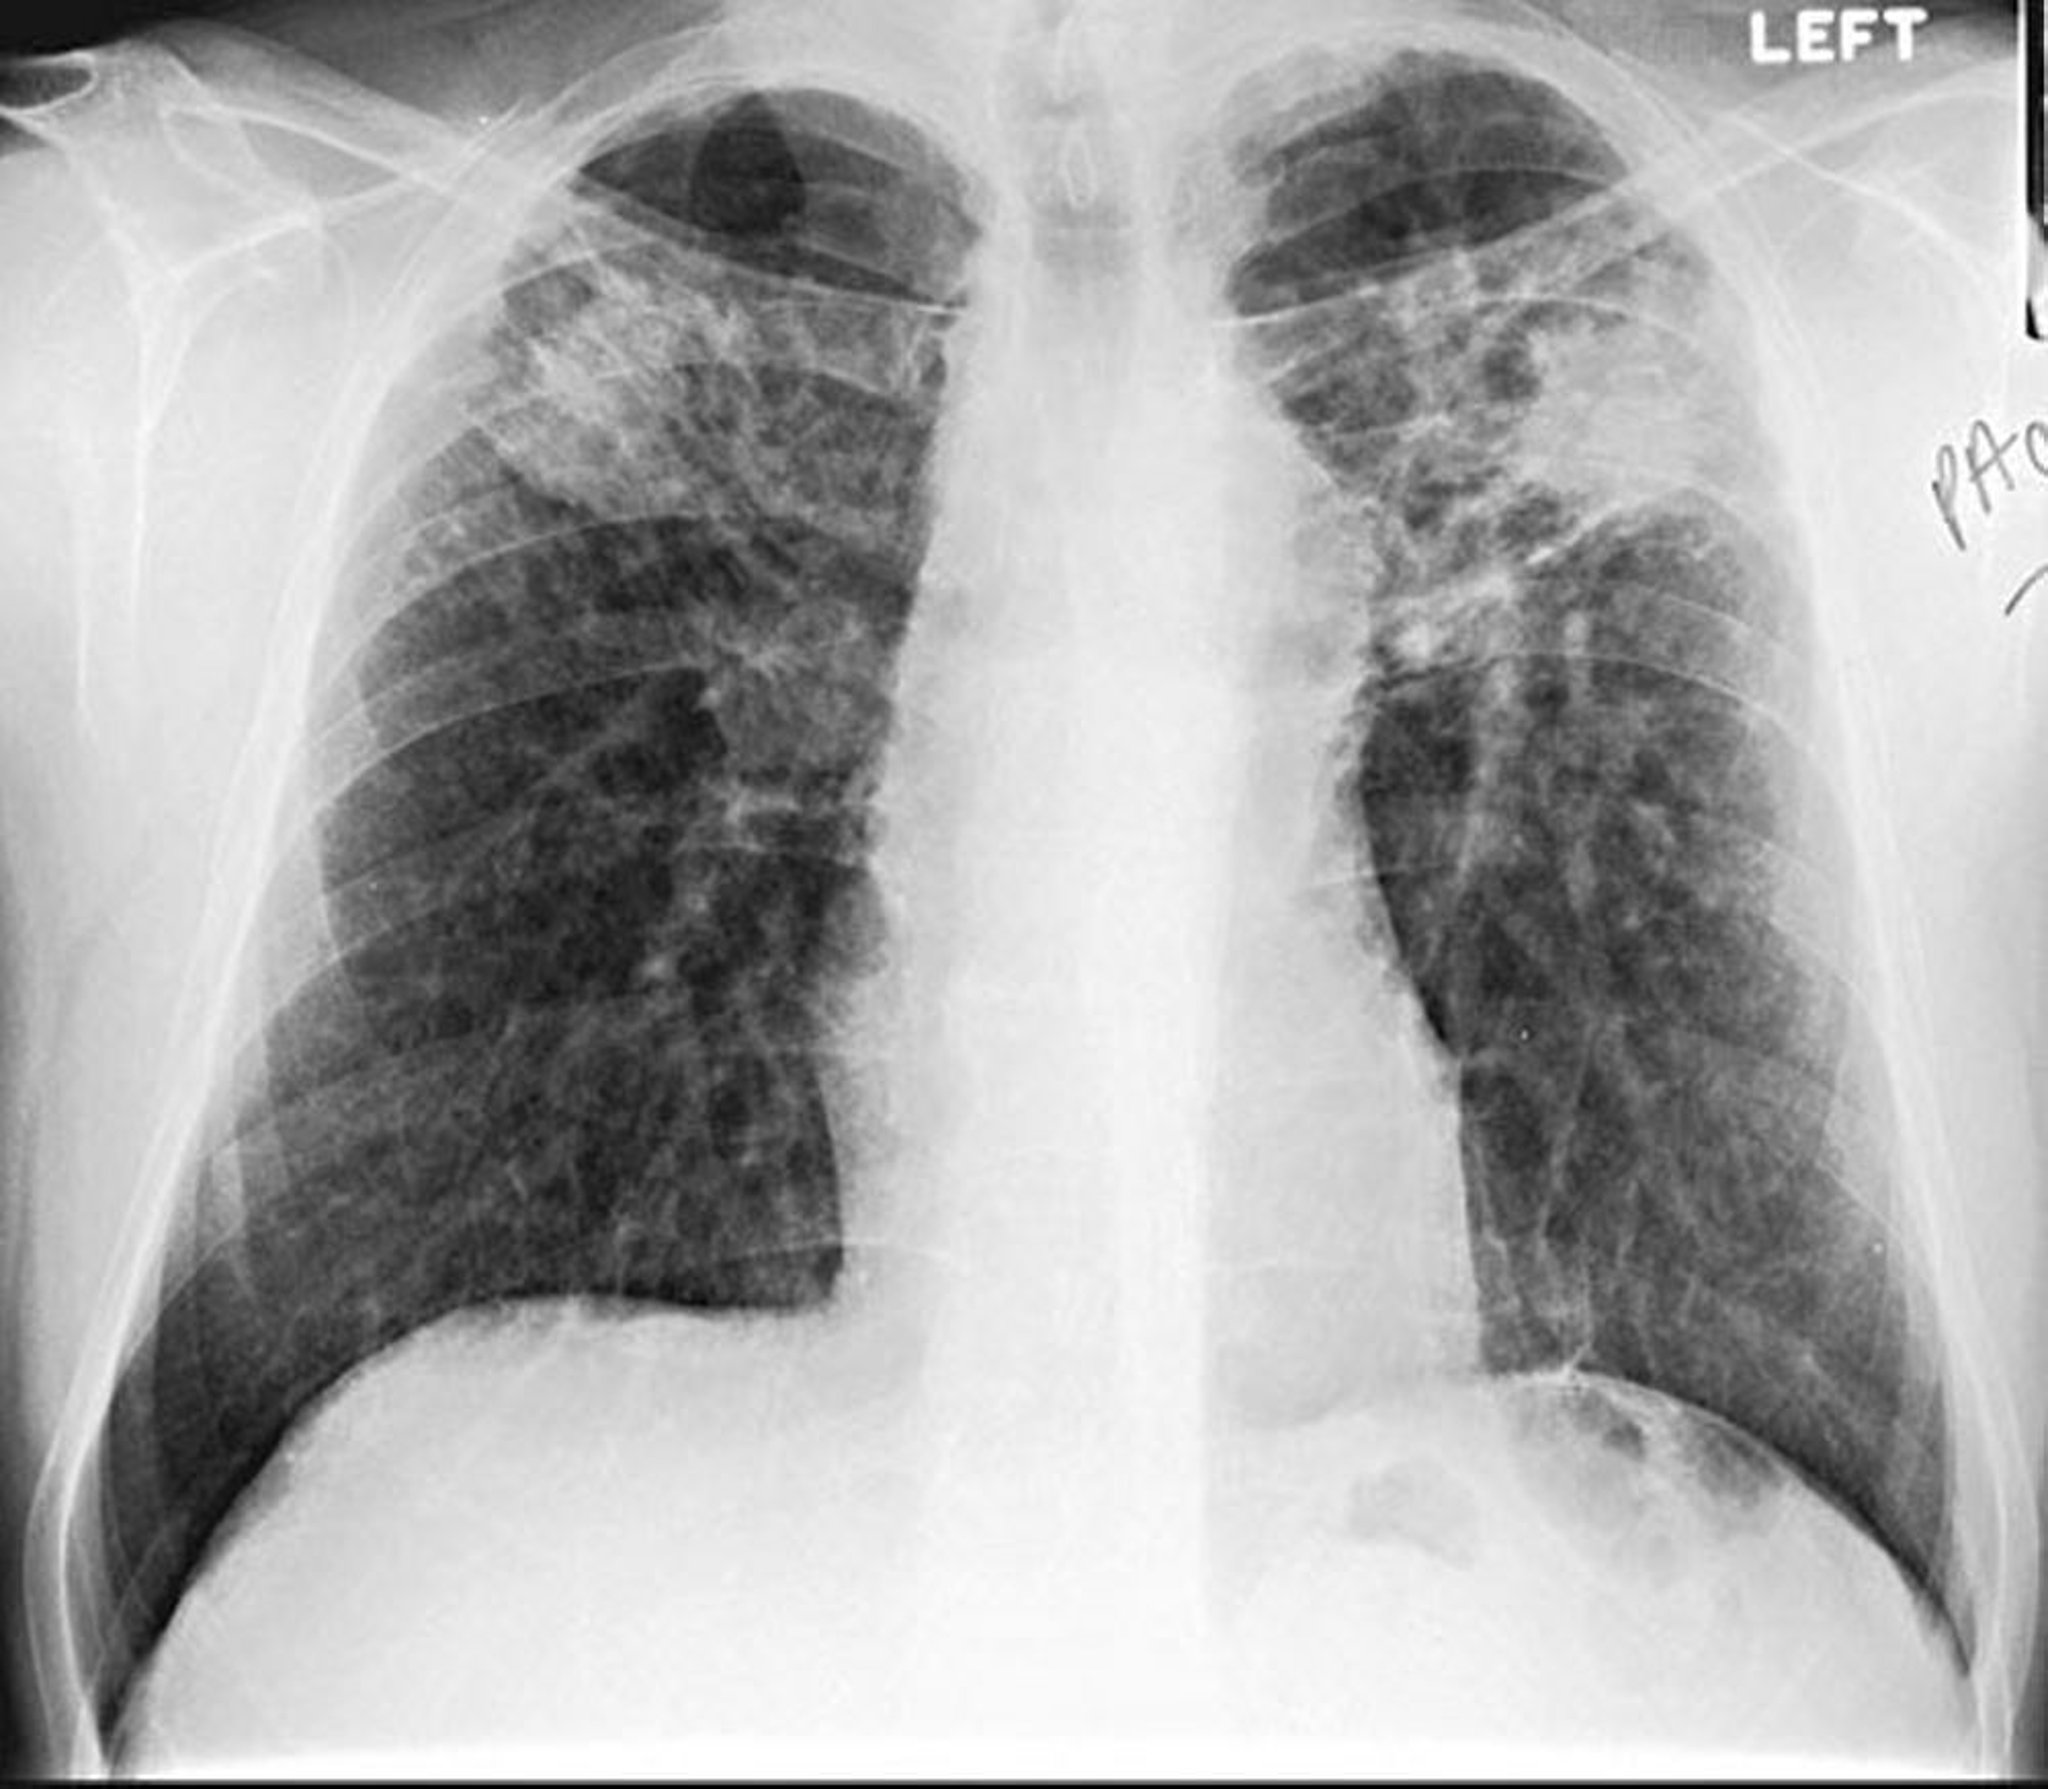

Bệnh bụi phổi – Thể kết khối

Hình ảnh do bác sĩ David W. Cugell cung cấp

Silicosis